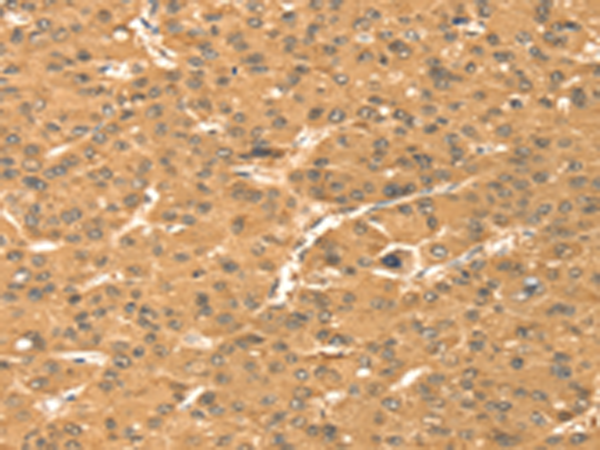

分类: 科研抗体货号: P01639别名: LANP; MAPM; PP32; HPPCn; PHAP1; PHAPI; I1PP2A; C15orf1应用: WB,IHC反应种属: Human